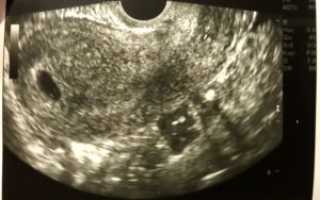

На пятой неделе беременности многие женщины испытывают волнение, но могут разочароваться, если на УЗИ эмбрион не виден. Это вызывает беспокойство о здоровье и развитии плода. В статье рассмотрим причины, по которым на этом этапе эмбрион может не обнаруживаться, и что это значит для будущих мам. Понимание этих аспектов поможет женщинам лучше ориентироваться в своем состоянии и снизить тревожность.

На 5 неделе беременности эмбрион может быть слишком мал, чтобы его можно было увидеть на ультразвуковом исследовании. Обычно в этот период размер эмбриона составляет всего несколько миллиметров, и его трудно различить. Кроме того, точность УЗИ зависит от оборудования и квалификации специалиста.

Развитие эмбриона: На 5 неделе беременности эмбрион находится на стадии, когда его размеры очень малы — всего около 1-2 миллиметров. В этот период он еще не имеет четко выраженных черт, и его сложно визуализировать на УЗИ. Эмбрион активно развивается, но его структура еще не сформирована до такой степени, чтобы быть видимой.

Ультразвуковая визуализация: На ранних сроках беременности ультразвуковое исследование может не показать эмбрион из-за его небольшого размера и положения в матке. Кроме того, качество аппарата и опыт врача также могут влиять на возможность увидеть эмбрион на этом этапе.

Формирование плаценты: На 5 неделе беременности начинается процесс формирования плаценты, которая будет обеспечивать эмбрион питательными веществами и кислородом. Этот процесс также влияет на то, как и когда эмбрион становится видимым на УЗИ, так как плацента начинает развиваться и может затенять эмбрион на ранних сроках.